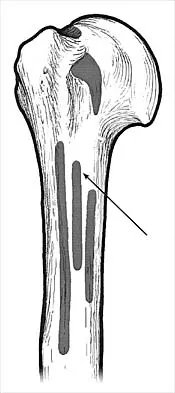

What muscle attaches to the site shown by the arrow in Figure 2?